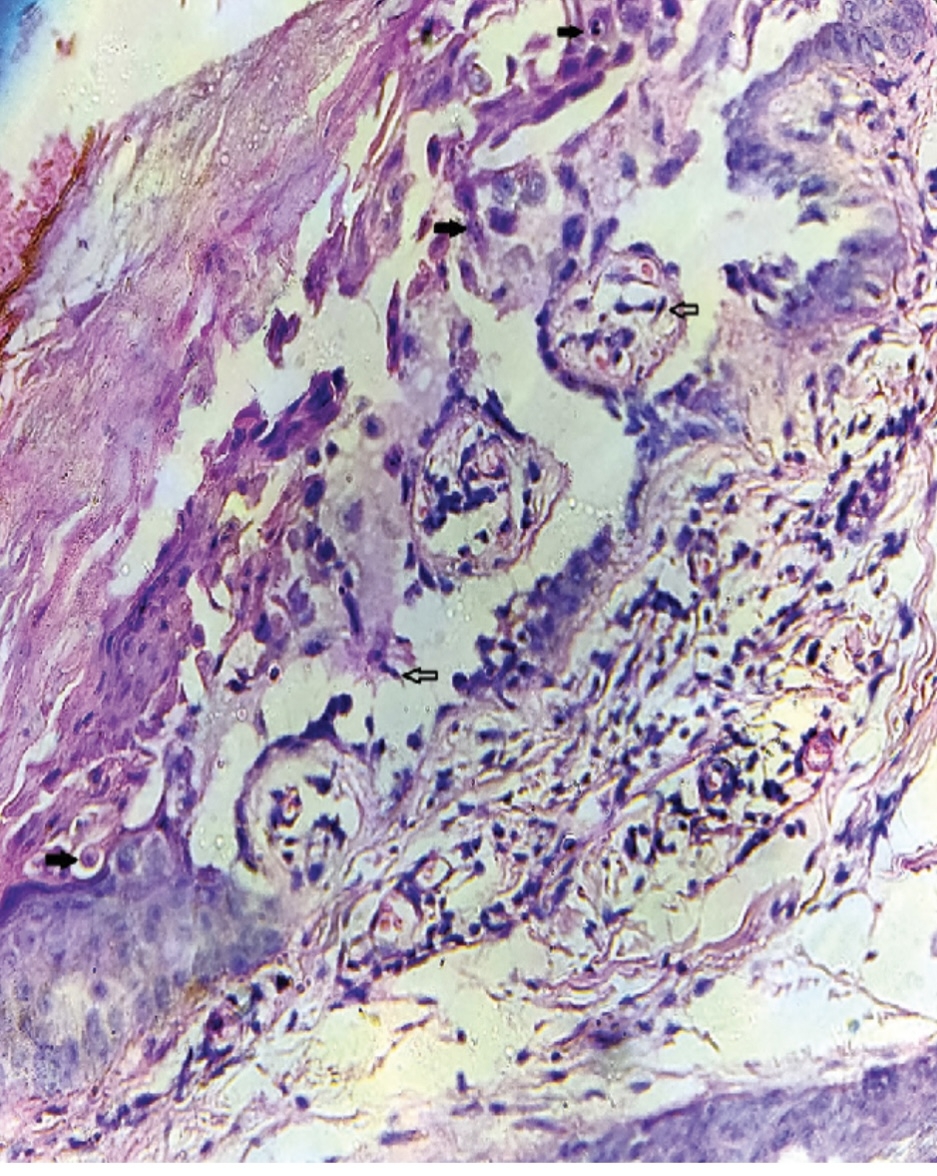

Abstract Body (Do not enter title and authors here): Darier’s disease (DD) is a rare autosomal dominant dermatologic disorder caused by mutations in the ATP2A2 gene, which encodes the sarco/endoplasmic reticulum Ca2+-ATPase pump (SERCA2). While DD is classically characterized by hyperkeratotic papules, nail changes, and mucosal involvement, ATP2A2 is also abundantly expressed in cardiac myocytes, where SERCA2a plays a central role in calcium handling and myocardial contractility. I present a unique case of dilated cardiomyopathy (DCM) in a 22-year-old male with longstanding, biopsy-confirmed DD. The patient developed progressive exertional dyspnea, orthopnea, and declining functional capacity. Dermatologic examination showed discrete hyperkeratotic papules in flexural areas and longitudinal erythronychia with distal splitting of fingernails. Echocardiography revealed global hypokinesis, dilated cardiac chambers, and a reduced left ventricular ejection fraction of 28%. Extensive evaluation excluded ischemic, infectious, autoimmune, and metabolic causes. Genetic testing identified a pathogenic heterozygous ATP2A2 mutation. Given the known cardiac expression of SERCA2a, a mechanistic link between the patient’s cutaneous and cardiac phenotypes was strongly considered. To my knowledge, this represents one of the few documented cases highlighting a potential association between DD and cardiomyopathy. This case expands the phenotypic spectrum of ATP2A2 mutations and underscores the need to consider cardiac screening in symptomatic DD patients. Recognition of such systemic associations is essential for early diagnosis, personalized care, and appropriate multidisciplinary management. Further investigation into the cardiovascular manifestations of ATP2A2-related disorders is warranted.